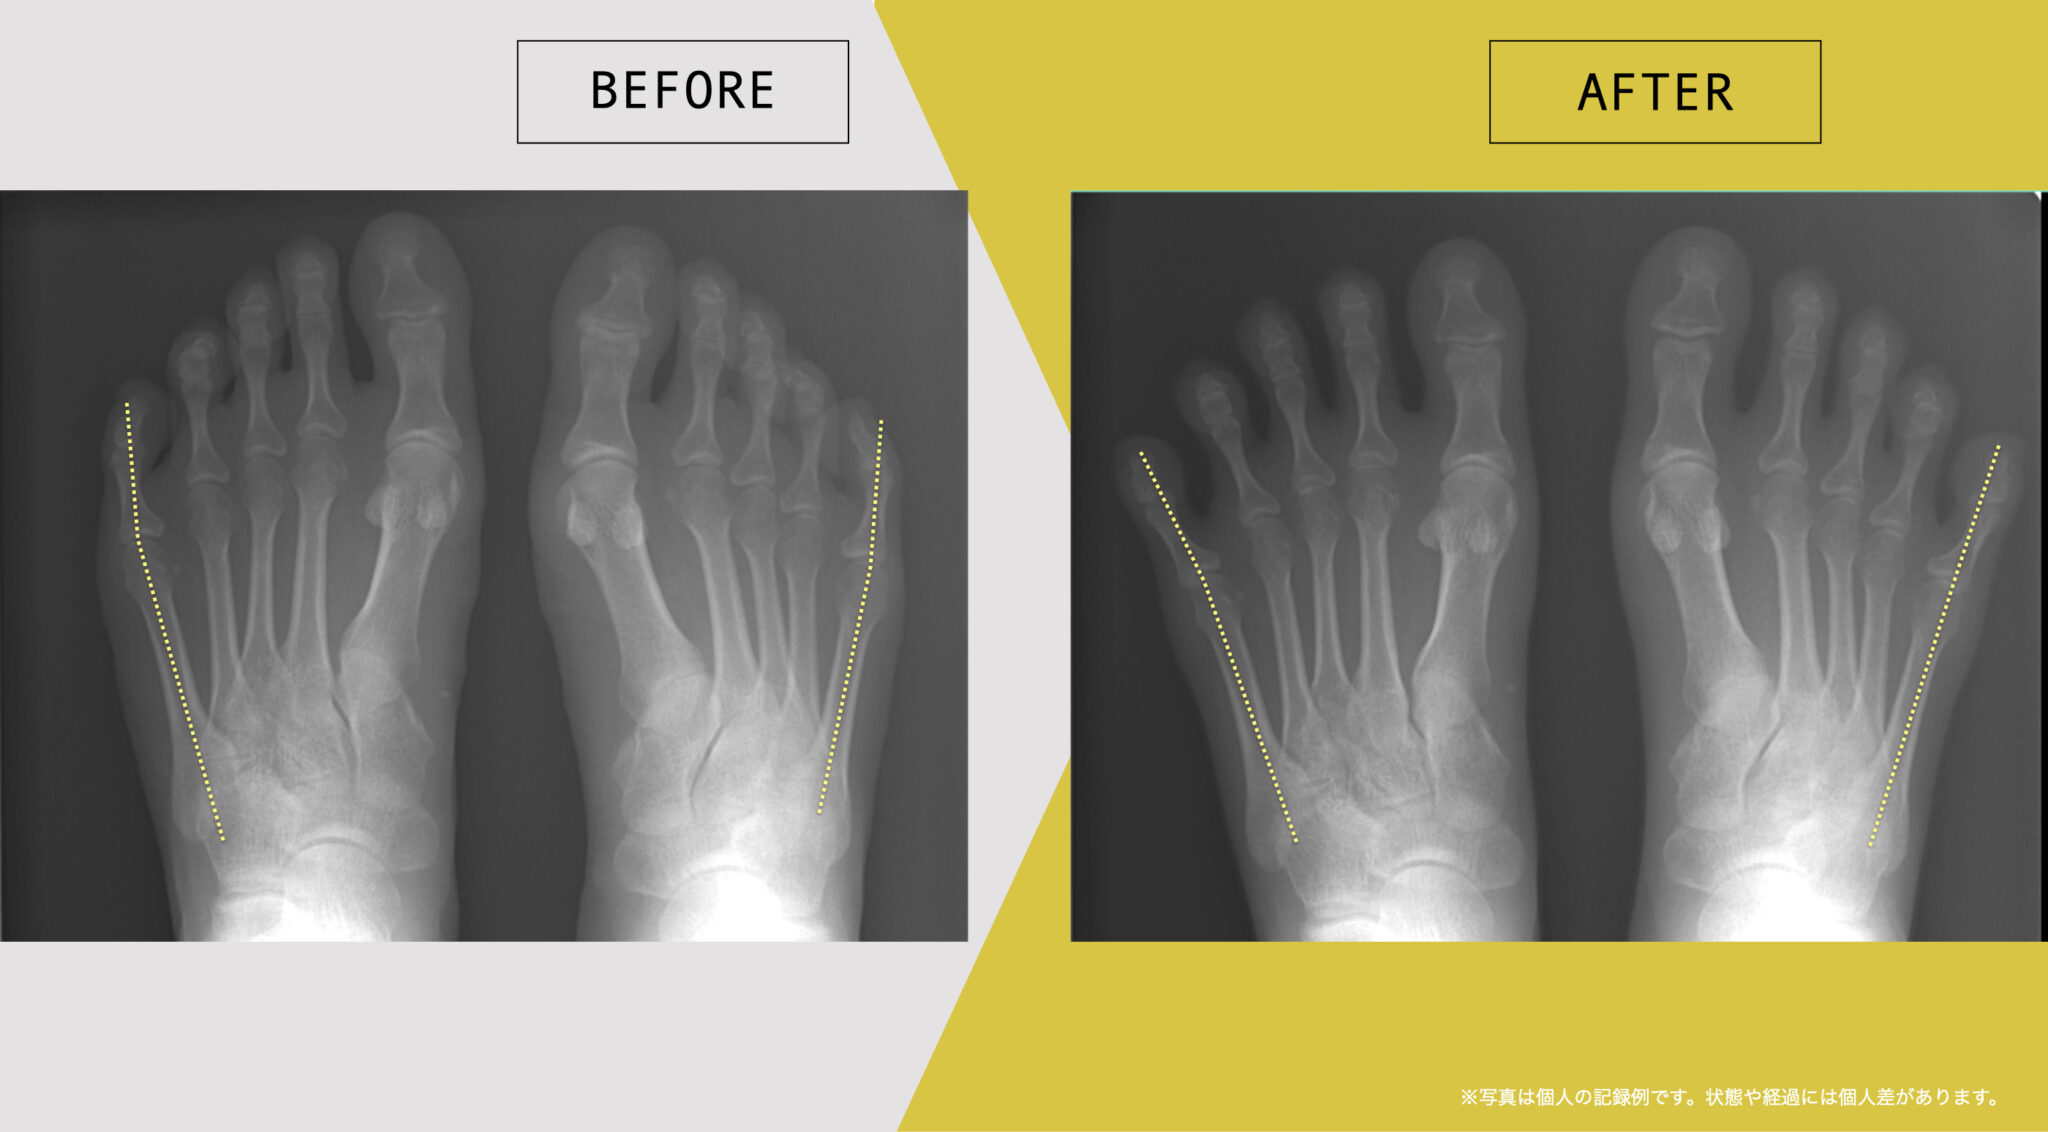

東京大学名誉教授・石井直方先生(運動生理学)とともに、2020〜2022年に行った共同研究では、YOSHIRO SOCKSの着用および、ひろのば体操を日常的に実践された方を対象に、内反小趾などに関する足指の状態や角度の変化について評価を行いました。

内反小趾角

開始時の内反小趾角は25.1°

8週間後の内反小趾角は5.3°

8週間目の平均値では、開始時と比べて、内反小趾角に19.8°の変化がみられました。

※開始前と8週間目の平均値の差

※グラフは臨床試験における平均値の推移を示したものです

※結果には個人差があり、すべての方に同様の変化が生じるわけではありません

※本データは石井直方名誉教授(東京大学)の助言を得て実施された研究に基づくものです